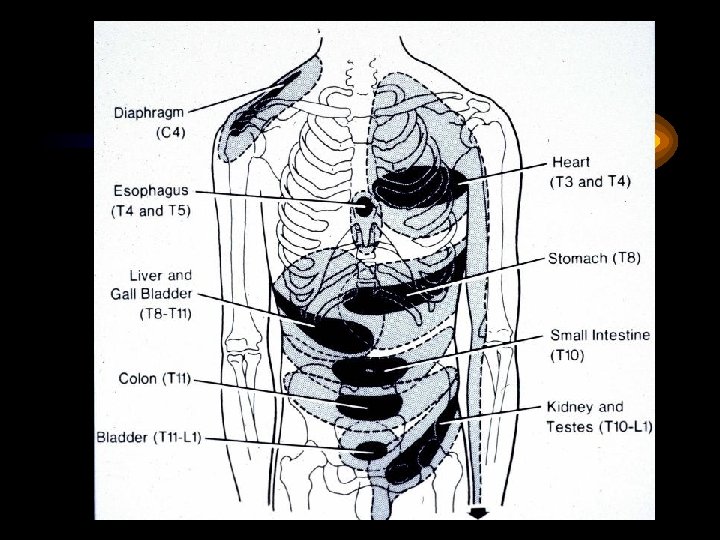

Ağrının Üç Tipi • Visseral • Somatik • Yansıyan

Visseral Ağrı • Otonom sinir sistemi iletilen ağrıdır. Organın uzağında duyulabilir ve yayılabilir. • Solma, soğuk terleme ve hipotansiyon gibi vazomotor reflekslerle beraber olabilir. • Organ—afferent lifler—MS—Beyin---MS--arka kök ---dermatom( her köke tekabül eden deri kuşağı)TALAMUSTA ALGILANIR • İç organlardan gelen uyarımlar deri ağrısını ileten lifleri ortak kullanır ve dolayısıyla ağrı o bölge cildinde hissedilir.

Somatik Ağrı • Kafa çiftleri ve MS’den etrafa giden duyu sinirlerinin ilettiği ağrıdır. BEYİN KORTEKSİNDE ALGILANIR • Sadece tahrişin olduğu yerde hissedilir, yayılma göstermez. • Pariyetel peritondaki spinal sinirlerin tahrişi ile uyanan ağrı, lokalize ağrıdır. (Apendisitteki sağ fossa iliakaya lokalize olmuş ağrı, divertikülitteki lokalize ağrı…)

Yansıyan Ağrı • Ağrı kaynağın olduğu yerden uzakta hissedilir. • Epigastrik ağrı inferior Miyokardial infarkt nedeniyle olabilir. • Sol omuz ağrısı dalak rüptürü habercisi olabilir (Kehr belirtisi)